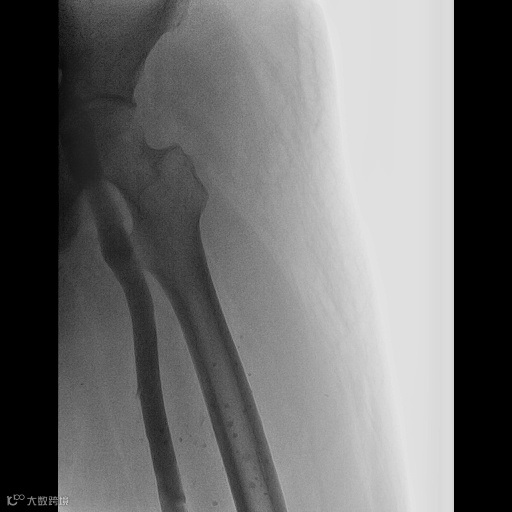

由沈阳市第一人民医院介入科陈建军主任团队运用中天天航™Pro血栓抽吸导管治疗一例急性左下肢深静脉血栓形成且伴有右下肢血流淤滞病变,成功清除血栓并快速恢复肢体灌注,欢迎大家阅读、分享、交流!

手术过程